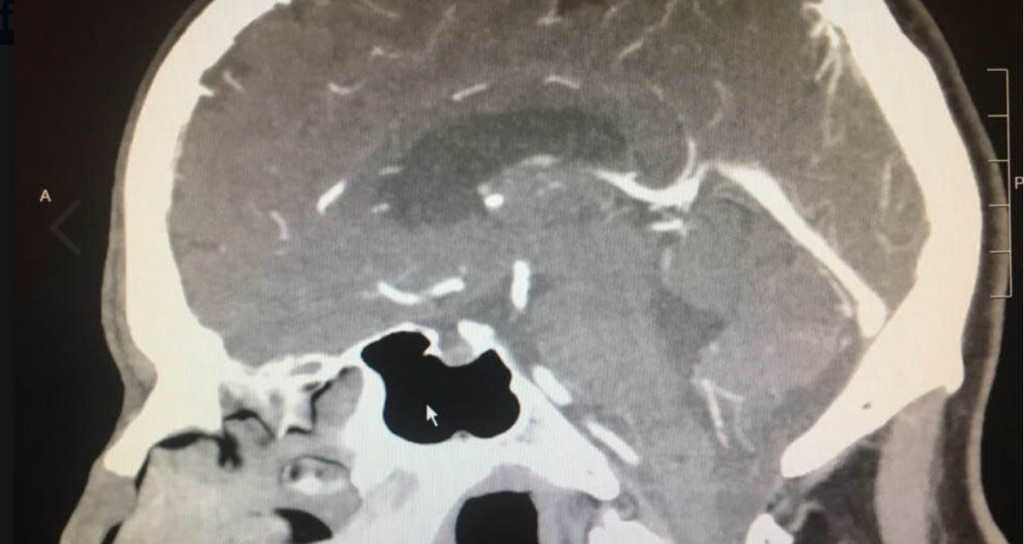

Then, the worst-case scenario became a reality. After several tests and scans, doctors confirmed Wood had a brain tumor and advised that he should undergo immediate surgery. Devastated by the news, but hopeful in God’s ultimate plan, the volunteer turned to the community that he’d spend decades serving, and requested just one thing: prayer. And boy did he get it.

Then, just as he was preparing to go in for surgery, something absolutely extraordinary happened: the doctors could find absolutely no trace of his brain tumor. They canceled the surgery and sent Wood on his way.

Still, the specialists did their best to understand the cause for Wood’s rapid remission. So far, it remains a complete mystery to them.

“We do tests and we have medical technology and we try to come up with some conclusion… sometimes things happen that we can’t explain,” said Dr. Richard Yee.